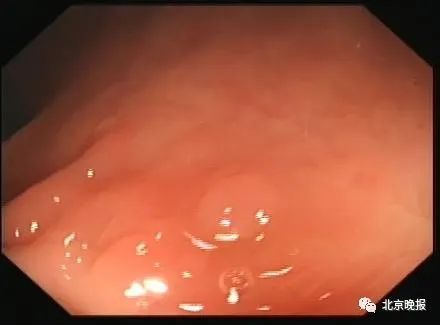

目前相关研究的结果并不一致。大多数学者倾向于结肠黑变病与后两者的发生没有直接关系。另一方面,由于结肠腺瘤或息肉不着色,小病灶在黑色背景下反倒更容易显现,更易被检出,这也可能是某些学者认为结肠黑变病增加结肠腺瘤发生的原因。

结肠黑变病背景下的小息肉病灶